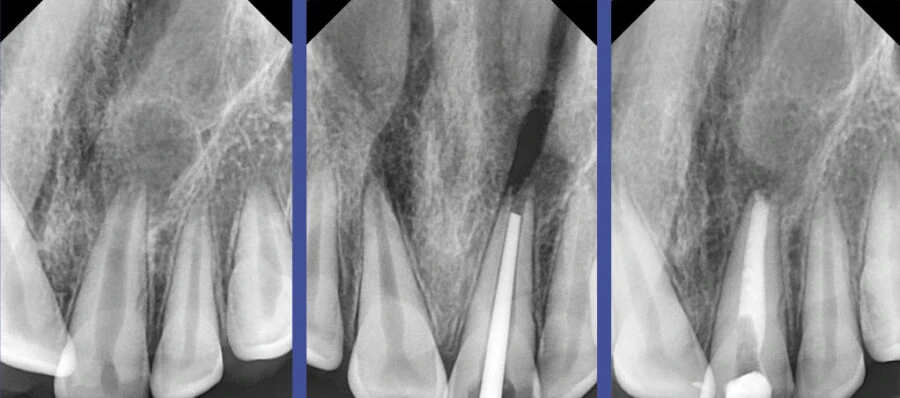

Bước 1: Chẩn đoán lại toàn diện

- Đánh giá lại X-quang: Sử dụng phim quanh chóp ở các góc độ khác nhau. Chụp Cone Beam CT (CBCT) là chỉ định cực kỳ giá trị để phát hiện ống tủy bỏ sót, đánh giá giải phẫu phức tạp và các tổn thương quanh chóp.